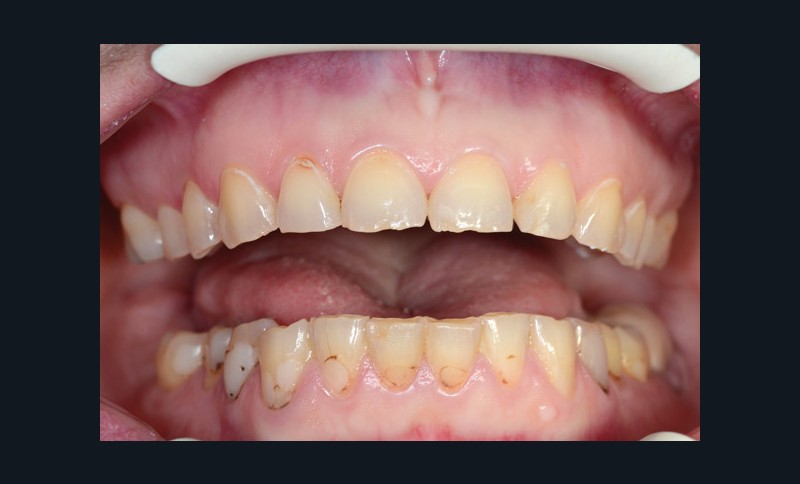

À l’examen clinique (fig. 2 à 4), on observe :

– des érosions sévères généralisées, symétriques et bilatérales (occlusales, palatines et vestibulaires au maxillaire) ;

– une usure des bords libres des incisives mandibulaires